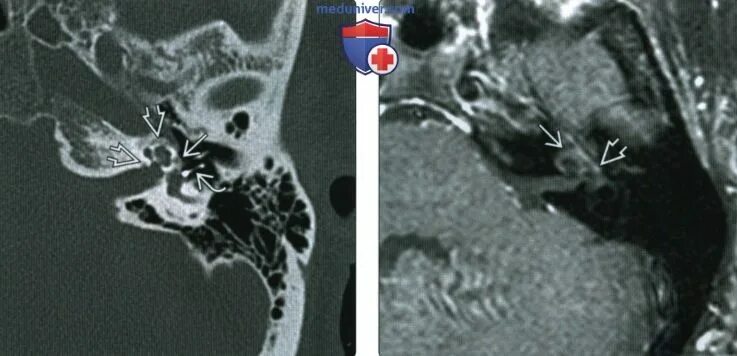

Кохлеарный отосклероз